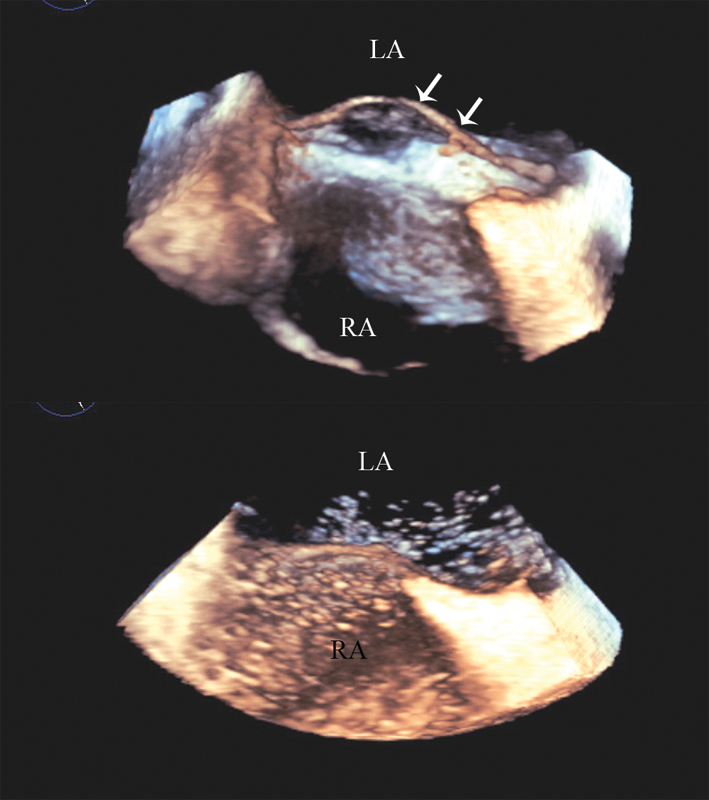

فحوصات تشخيصية لبعض امراض القلب والشرايين التاجية